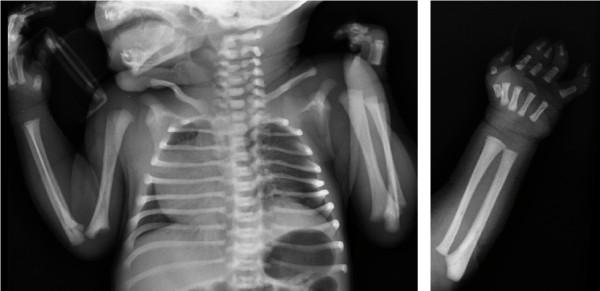

一例伴右旋移位的 Poland 综合征。

A case of Poland Syndrome associated with dextroposition.

Classical Poland Syndrome (PS) is characterized by unilateral, partial or complete absence of the sternocostal head of the major pectoral muscle and brachysyndactyly of fingers on the same side. We report the case of a newborn infant with dextrocardia and PS located on the left side. This association is very rare: to date only 19 cases have been described in scientific literature. In all reported cases, as in the present, the Poland defect involved the left side and was associated to rib defects, whereas most cases of PS are on the right side and few have rib defects. This case supports the view that dextrocardia follows the loss of volume of the left hemithorax caused by Poland sequence and that the combination of PS and dextrocardia is not coincidental.

摘要

经典波兰综合征(PS)的特征为单侧、部分或完全缺失胸大肌胸肋部和同侧手指短并指。我们报告了一例左侧发生右旋心和 PS 的新生儿病例。这种关联非常罕见:迄今为止,科学文献中仅描述了 19 例。在所有报道的病例中,与本例一样,波兰缺陷涉及左侧,并伴有肋骨缺陷,而大多数 PS 病例发生在右侧,很少有肋骨缺陷。该病例支持以下观点,即右旋心是由波兰序列引起的左侧胸腔容量丧失的结果,并且 PS 和右旋心的组合并非巧合。